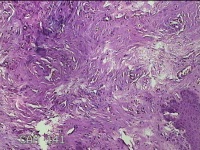

下唇肿物

性别

女

年龄

22岁

临床诊断

口腔黏液腺囊肿

一般病史

发现下唇肿物3月余。

标本名称

大体所见

灰白粉红色肿物0.6x0.3x0.2cm一个,表面光滑,切面灰白粉红色,质中。

良性病变。